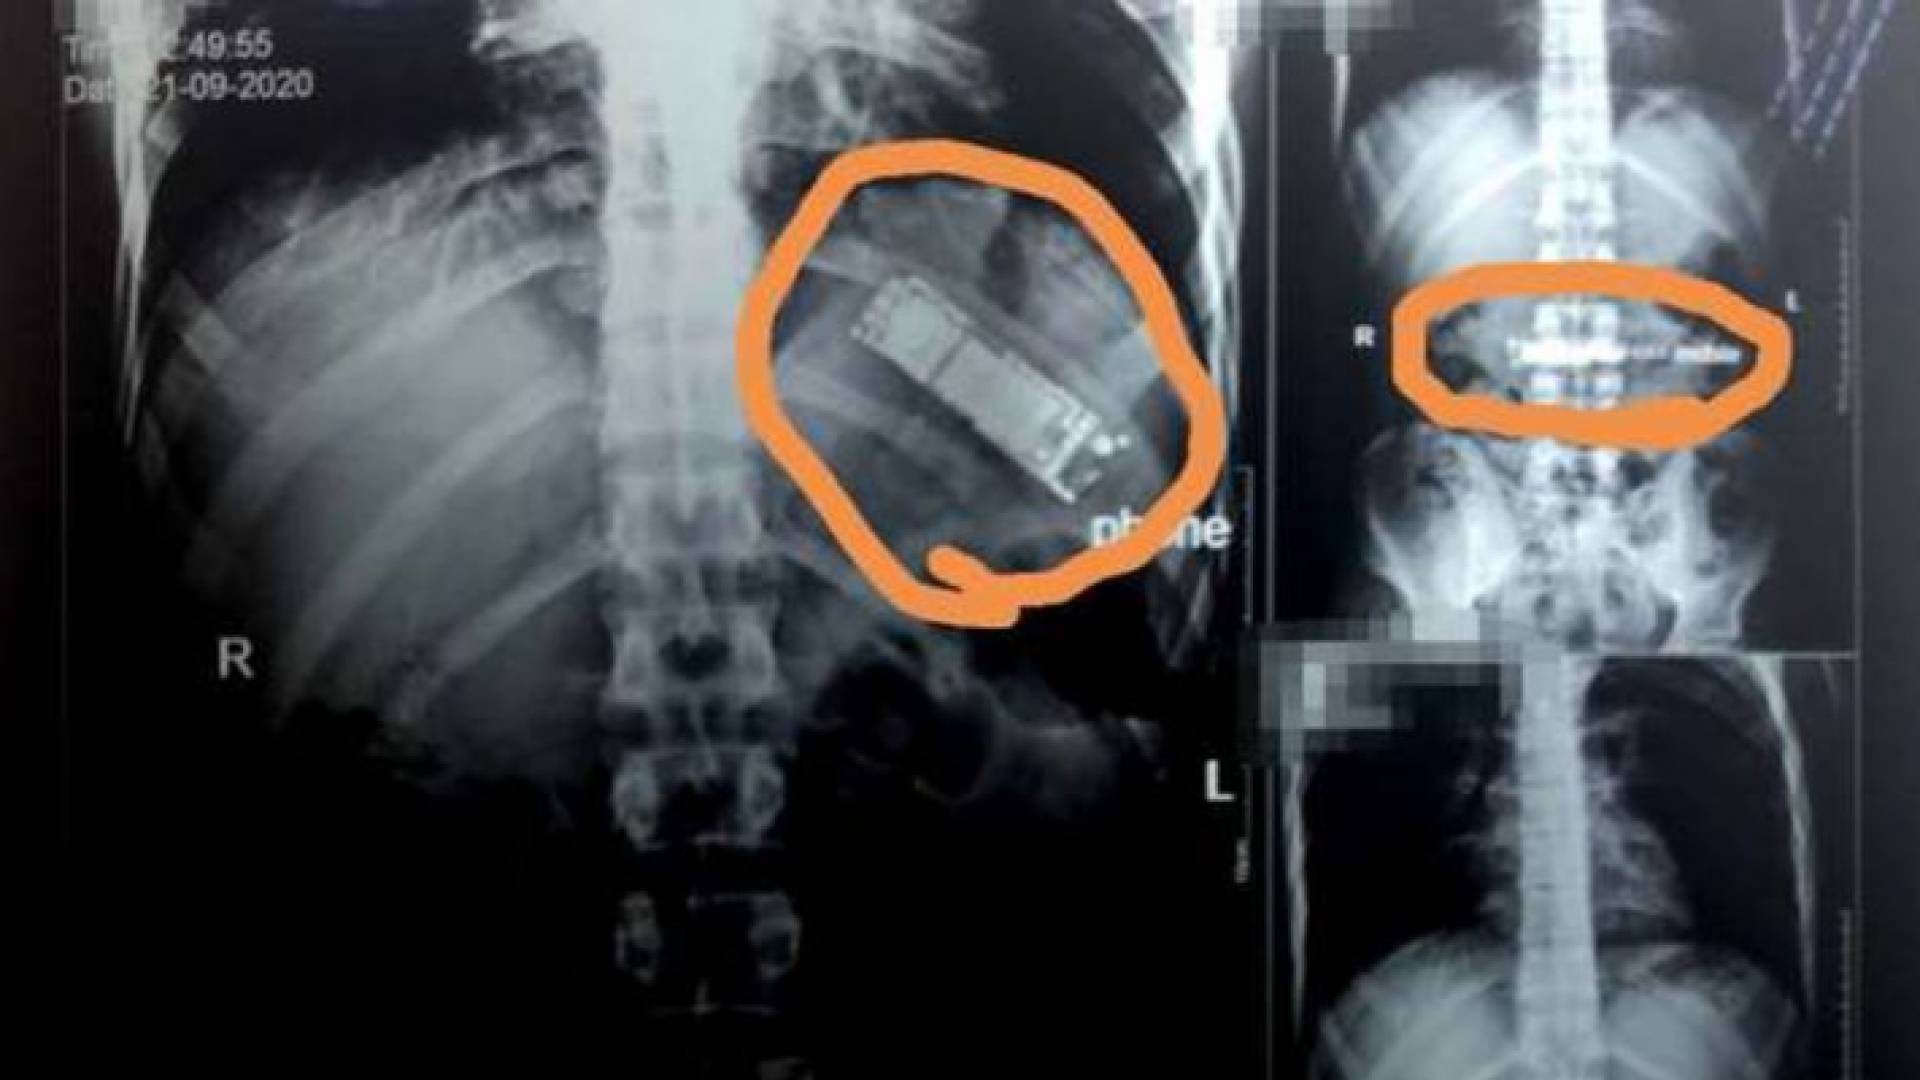

تفاجئ طبيب مصري بعد عثوره على هاتف محمول في معدة احد المواطنين المصريين.

وكشفت فحوص بالأشعة أجريت لمريض بمستشفيات بنها الجامعية في مصر، عن وجود هاتف محمول في معدته بقي هناك بعد أن قام بابتلاعه منذ 7 أشهر.

وقال الدكتور محمد الجزار، استشاري أورام الصدر وأستاذ جراحة القلب والصدر والمناظير بكلية الطب في جامعة بنها، إنه تم استقبال المريض اليوم، من مدينة كفر شكر بالقليوبية، وتم إجراء أشعة تليفزيونية على الصدر والبطن، حيث تم اكتشاف وجود هاتف محمول بمعدته.

وأوضح الجزار، أن المريض أكد أنه ابتلع الجهاز منذ 7 أشهر على سبيل المداعبة مع أصدقائه دون أن يعلم أي فرد من أبناء أسرته، موضحا أنه بسؤاله عن سكوته طوال هذه الفترة، أكد أنه كان يظن أن التليفون سيخرج بمجرد حدوث استرجاع بالمعدة مرة أخرى، إلا أن هذا لم يحدث حتى الآن.

وتابع الطبيب، أنه تم تحويل المريض لقسم الجراحة العامة بالمستشفى، ويتم إعداده حاليا ووضعه بقائمة الجراحات تمهيدا لإجراء الجراحة سريعا والتعرف على نوع التليفون وكيفية ابتلاعه.